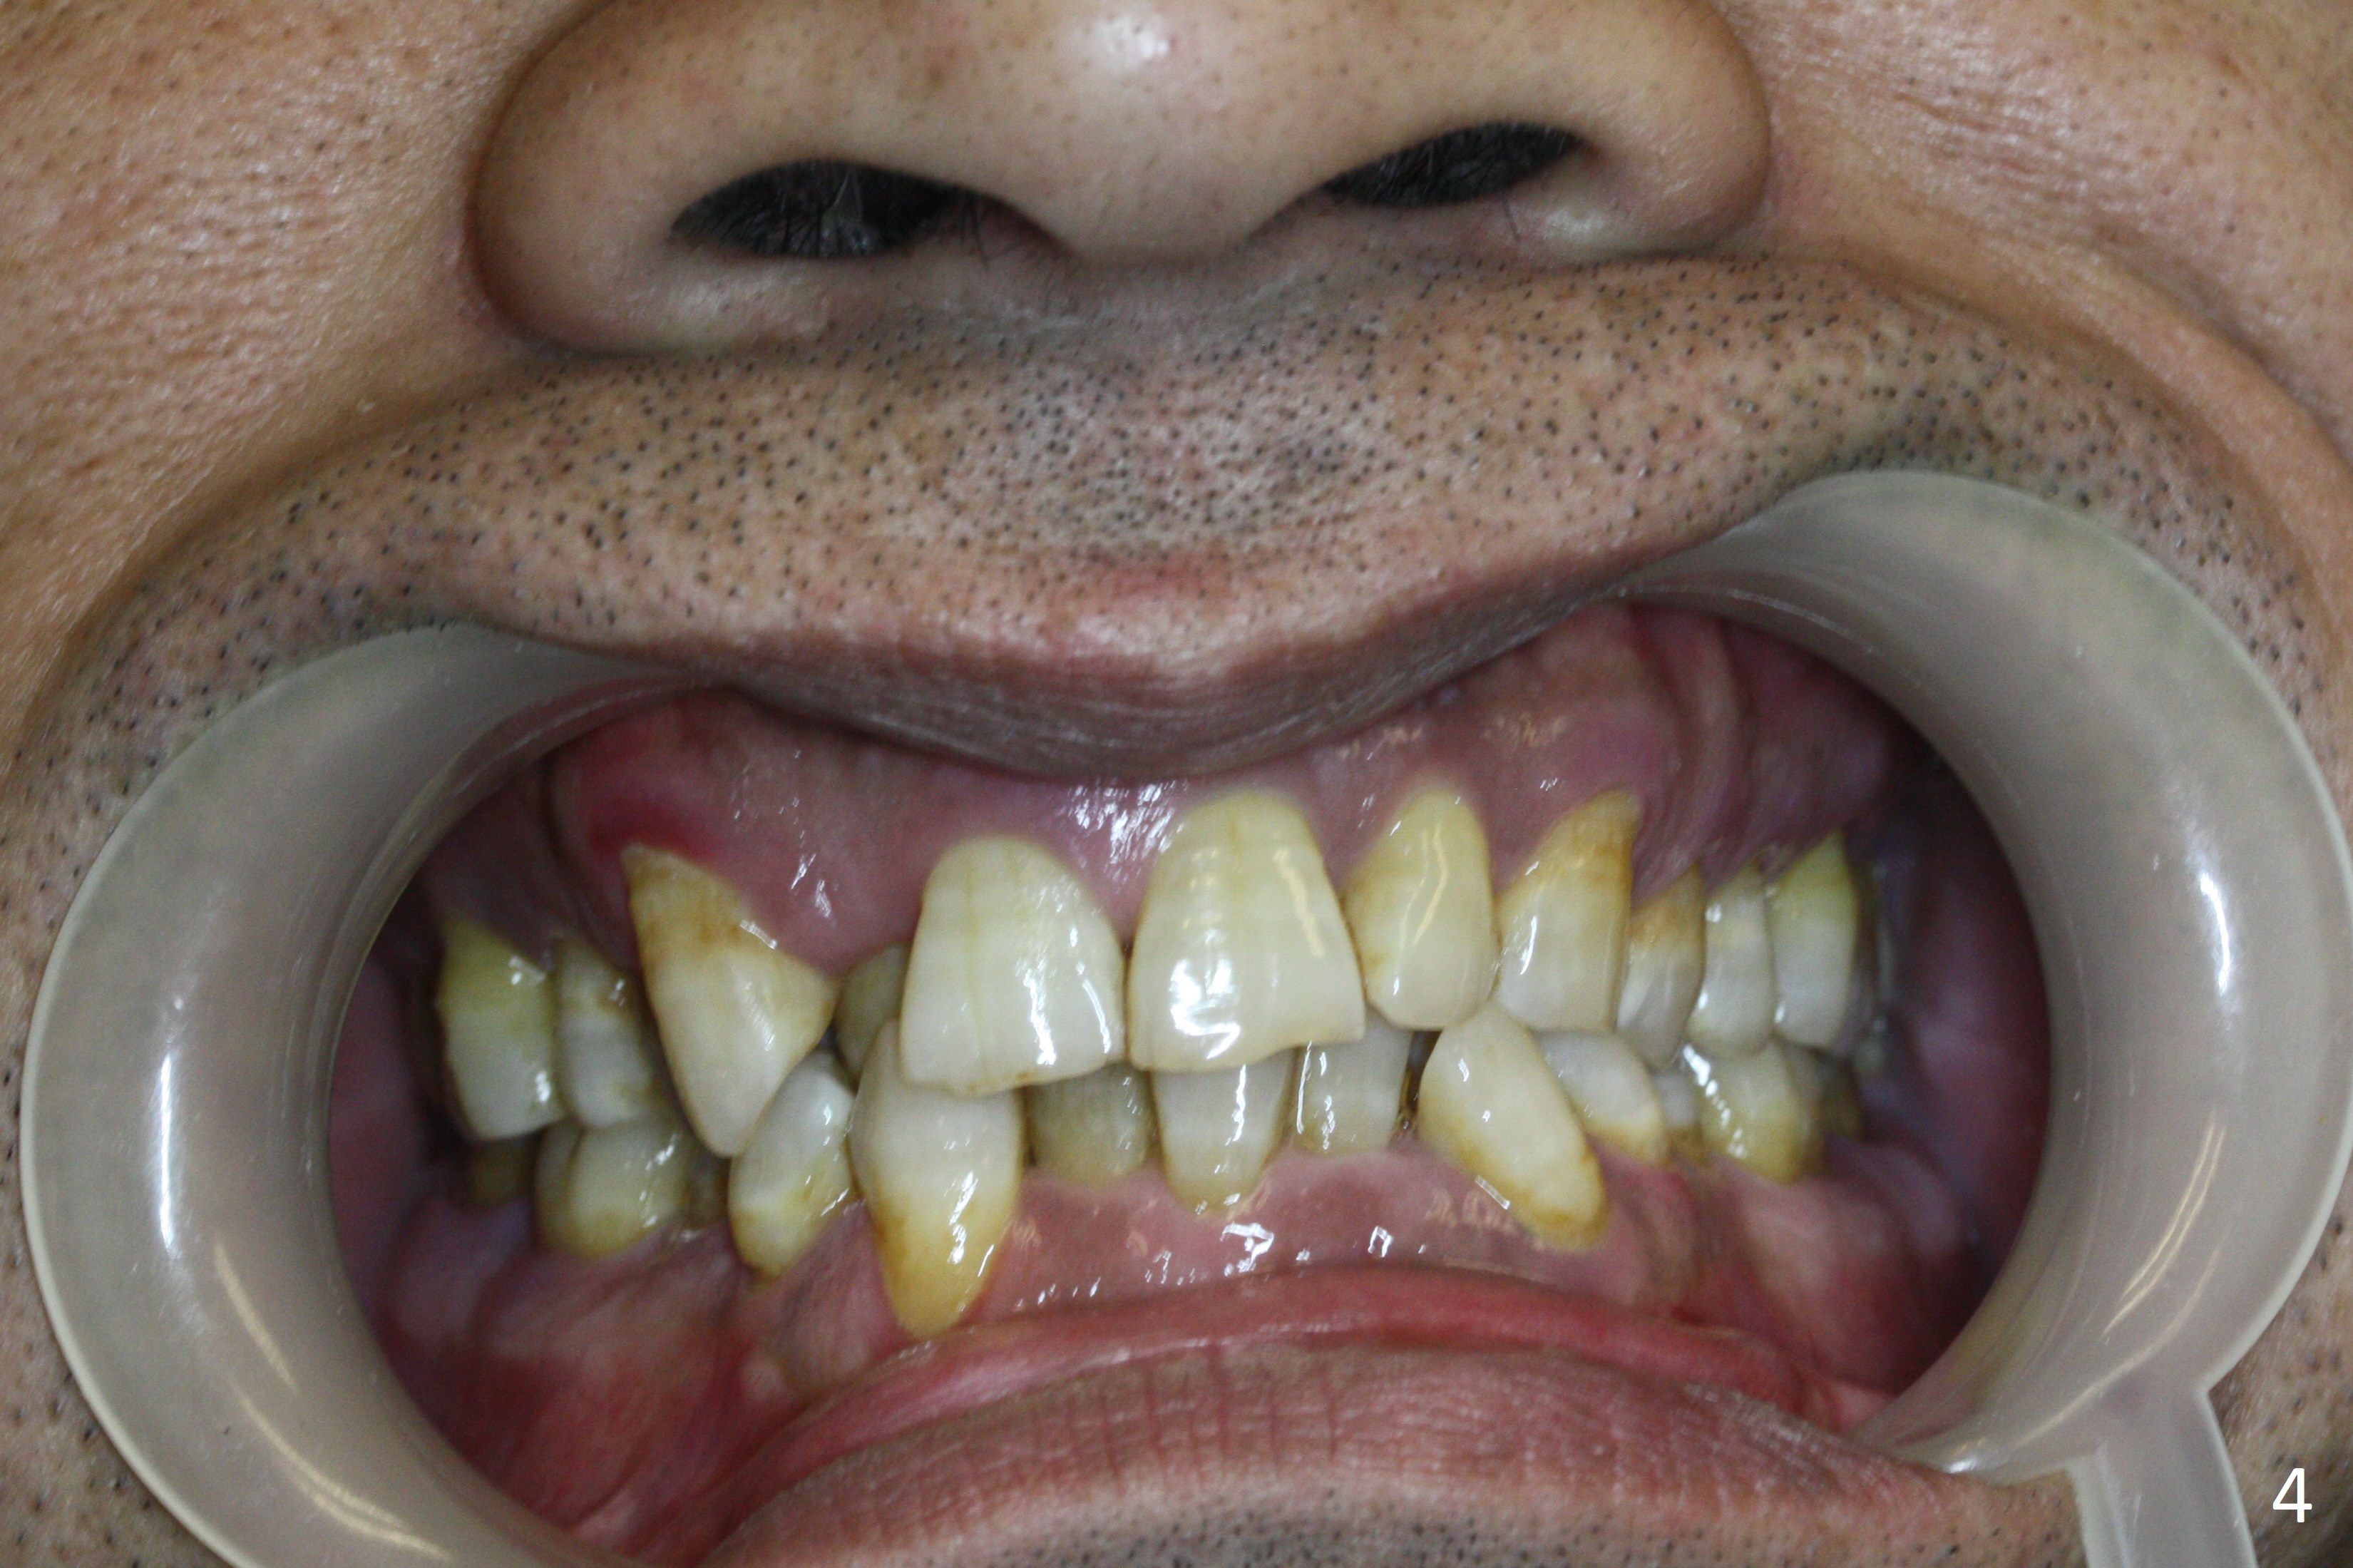

Enough Space For Crowding After Extraction? A 47-year-old man requests orthodontic treatment following SRP in other office (Fig.1-11). For severe crowding and midline shifting, extraction of four of the 1st bicuspids is imminent. Is it enough? To answer the question, model surgery is performed (Fig.12-16). 1st visit: periodontal maintenance, orthodontic consent (emphasizing oral hygiene) extract 4s and possibly L8s and separators. The beauty of this vist is that after local anesthesia and extraction including L8s, it is painless and easy to remove calculus from the proximal surfaces of the neighboring teeth. It is much easier to place separators after extraction. It is expected that there is no gingival erythema when the patient returns for bracketing. Take photos of UR3, similar to Fig.3. Molar banding is also anticipated to be easy with separator placement after extraction. Return to Ortho Cases Xin Wei, DDS, PhD, MS 1st edition 11/23/2017, last revision 04/28/2019